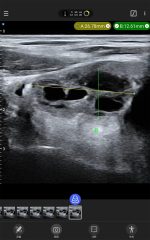

Galería de demostración

|